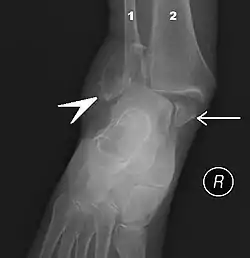

В ходе объективного обследования применяются физикальные методы исследования: осмотр, пальпация. Немаловажное значение имеет тщательный сбор анамнеза. Из инструментальных методов большое распространение получило рентгенологическое исследование голеностопного сустава в прямой, боковой, а также косой проекции. В настоящее время для диагностики применяют также артроскопию.

При растяжении связок голеностопного сустава быстро развивается отек вследствие кровоизлияния с внутренней или наружной стороны сустава, появляются резкие боли при подвертывании стопы внутрь. При пальпации под лодыжками ощущается резкая болезненность. Если одновременно с растяжением связок происходит перелом V плюсневой кости, то определяется резкая боль при пальпации её основания.

Вывихи и подвывихи в голеностопном суставе комбинируются с переломами лодыжек. Вывих может возникнуть в месте соединения таранной и пяточной кости. В этом случае отмечаются значительное утолщение и деформация голеностопного сустава и пяточной области. Пятка подвернута внутрь.